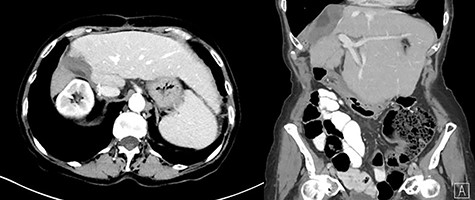

The postoperative course was uneventful notably without hepatic encephalopathy, gastrointestinal bleeding or ascites formation. The liver function tests remained within normal limits. The AFP further dropped to 4.8 and 4.4 ng/ml, at 1 month and 6 months respectively, following surgery. Six months postoperatively, abdominal ceCT scan did not show residual tumor (Fig. 7).

Six-month postoperative ceCT showing no residual tumor; post-surgical changes are seen along the cut edge of the liver status post right hepatectomy.